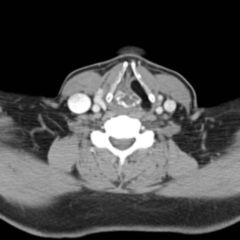

Bei der Kehlkopfspiegelung oder bei der Untersuchung mit dem Lupenlaryngoskop finden sich, meist an der freien Stimmlippenkante und im hinteren Drittel des Stimmbandes, blassrötliche bis düsterrote, häufig kugelige Gebilde, die im Fall von Intubationsgranulomen über erbsgroß und auch gestielt sein können. Solche gestielten Granulome können gelegentlich abreißen und geschluckt oder abgehustet werden, was zu einer Spontanheilung führen kann. Unter dem Operationsmikroskop erkennt man, dass Intubationsgranulome nicht von Epithel überzogen sind.

Kontaktgranulome finden sich an korrespondierender Stelle im hinteren Drittel des Stimmbandes, häufig asymmetrisch, indem das vorspringende Granulom einer Seite sich bei der Phonation in eine Auskehlung der Gegenseite presst. Kontaktgranulome können im Zuge narbiger Veränderungen von Epithel überzogen werden, das in Einzelfällen auch Verhornung zeigen kann.